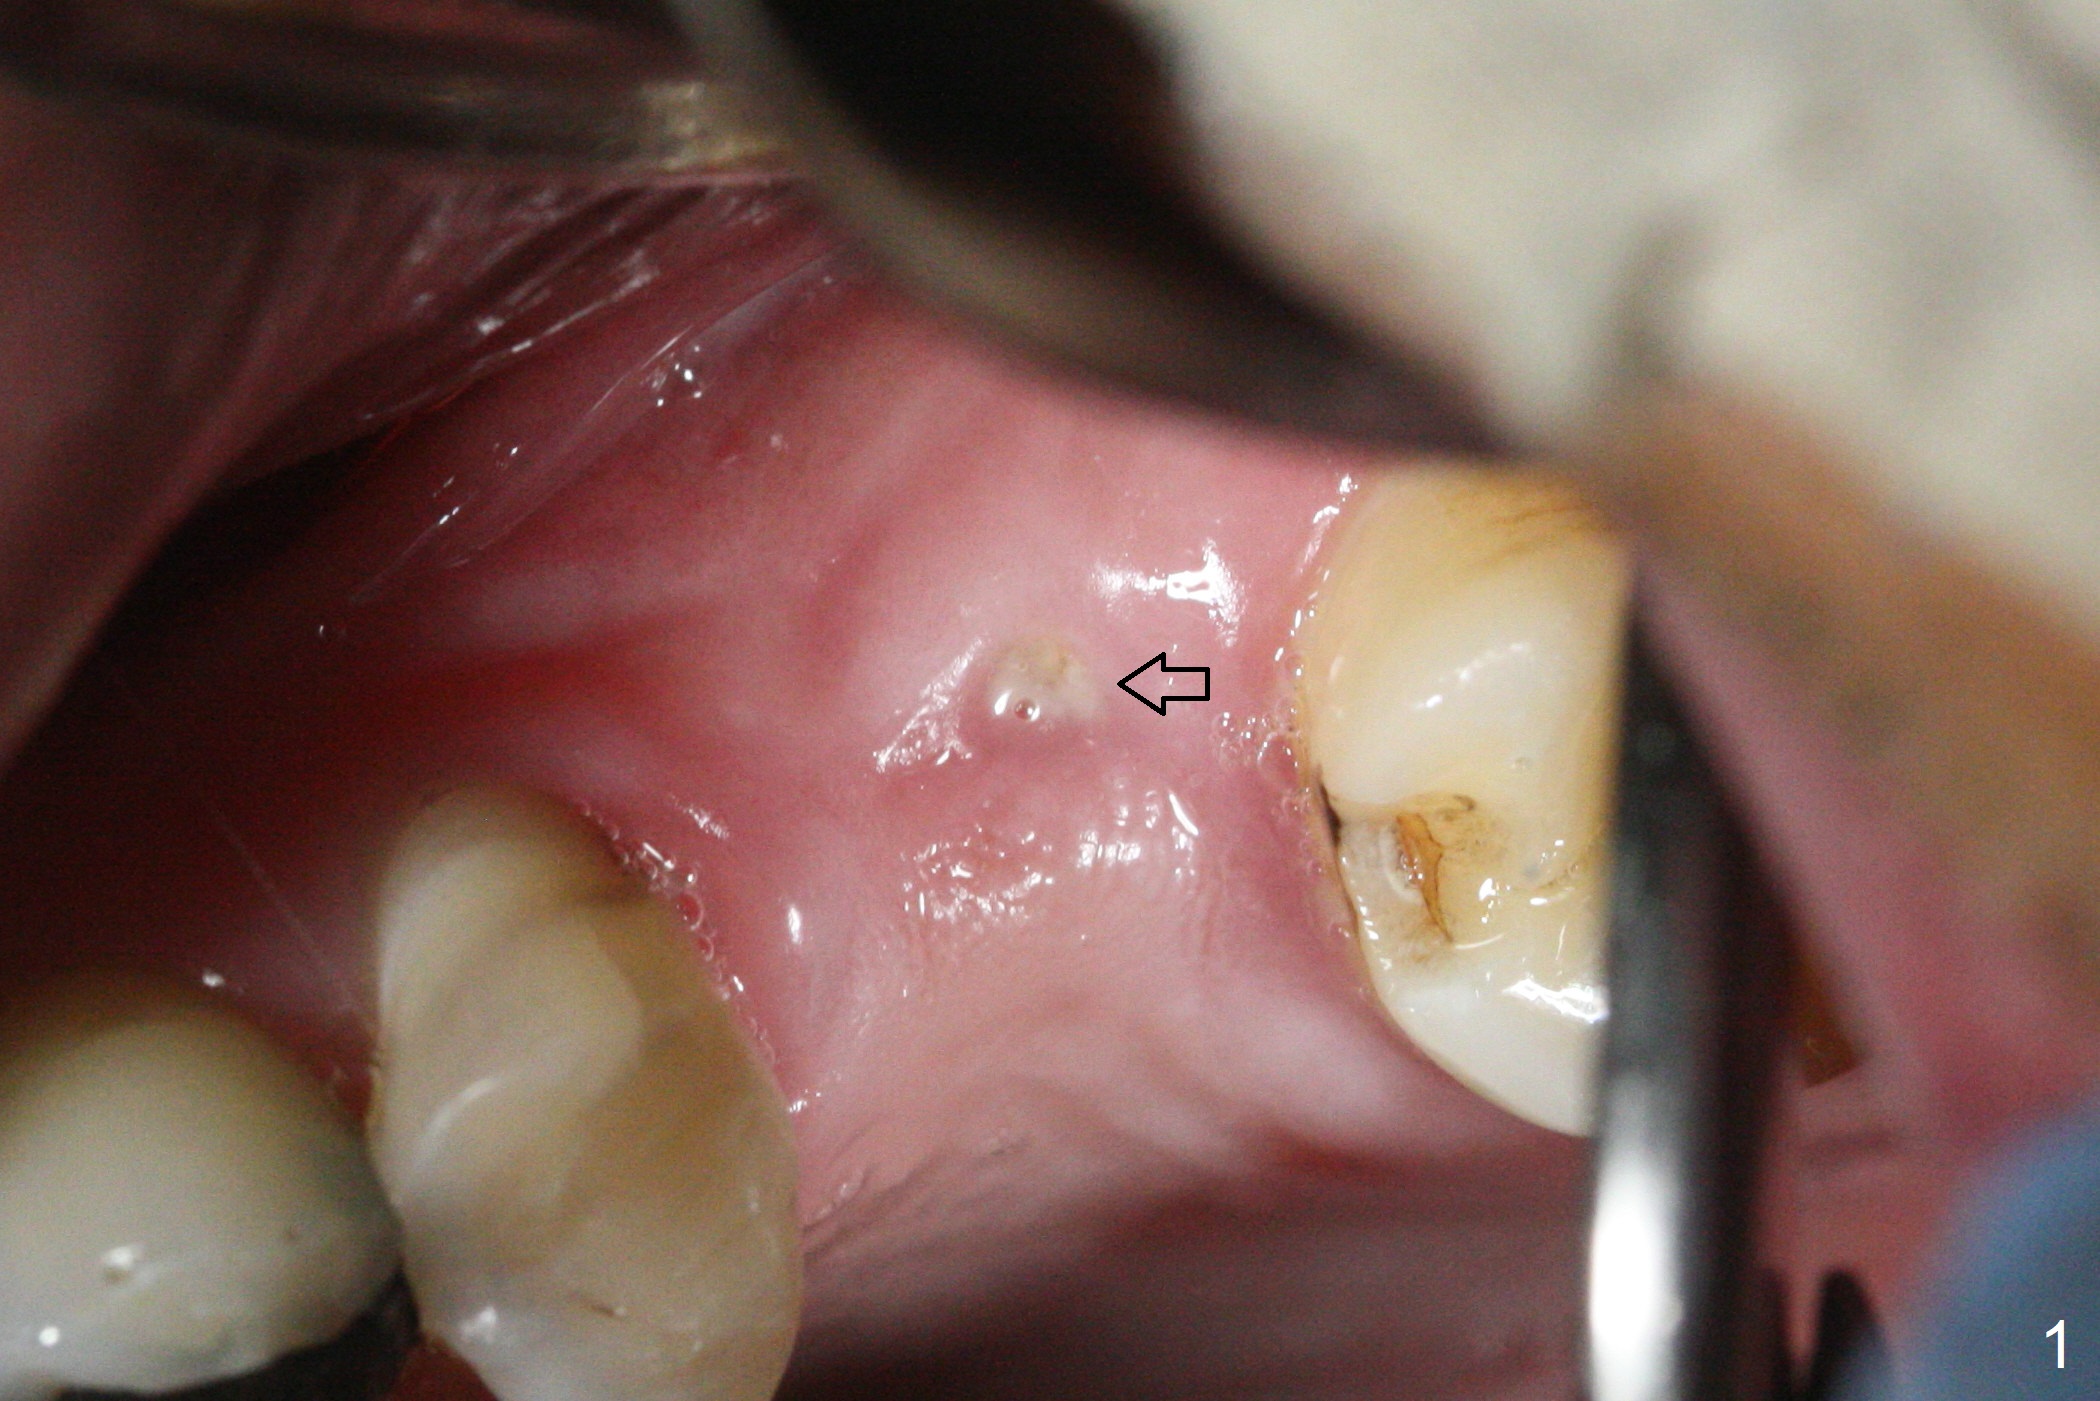

After extraction of the distobuccal residual root of the tooth #14 (Fig.1 arrow), the gingiva around the socket does not look like the keratinized one (Fig.2 *). An osteotomy through the distobuccal socket would seem too buccal for immediate implant. The palatal gingiva feels too tough to be stretched. An incision is made (Fig.3 dashed line); with elevation, the thick flap is transferred buccally (curved arrow). An osteotomy is initiated in the palatal bone with 1.5 mm drill, followed by Magic Expanders until 4.3 mm for 11 mm (Fig.4,5). Following Magic Drill 3.8x13 mm, the sinus membrane is found to be perforated. The latter is repaired with Osteogen plug. A 4.5x9 mm IBS implant is placed with 50 Ncm (Fig.6). Osteogen plug and allograft (Fig.7 *) are inserted into the remaining distobuccal socket (reduced after bone expansion). When a 5.5x4(4) mm abutment is placed, the transferred flap appears to be adapted to the distobuccal defect (Fig.8 *). Later one suture is placed for fixation. After provisional insertion, periodontal dressing is applied. Nine days postop, the periodontal dressing dislodges. When the loose provisional is removed for recementation, the flap seem to have healed (Fig.9 *). The gingiva heals around the abutment 5 months postop (Fig.9); the distal socket appears to heal while the bone graft remains at the crest (Fig.11,12). When #30 develops buccal abscess, the patient masticates on the left, leading to loss of composite at #13 (Fig.14); in fact the abutment at #14 is incompletely seated.